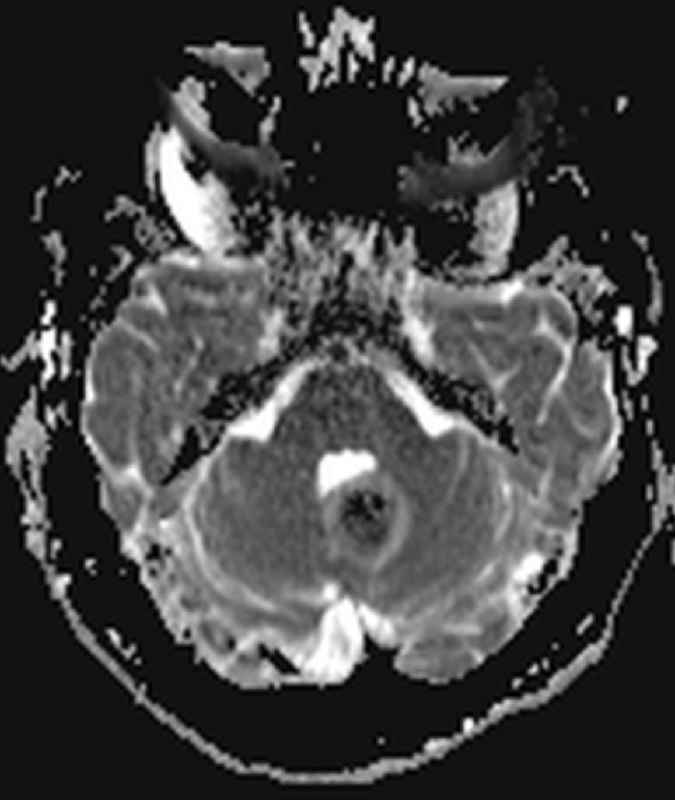

интересный случай! И не менее интересны ваши мнения! Мужчина 74 года.

в декабре 2020 удалена менингиома, а теперь - вот так